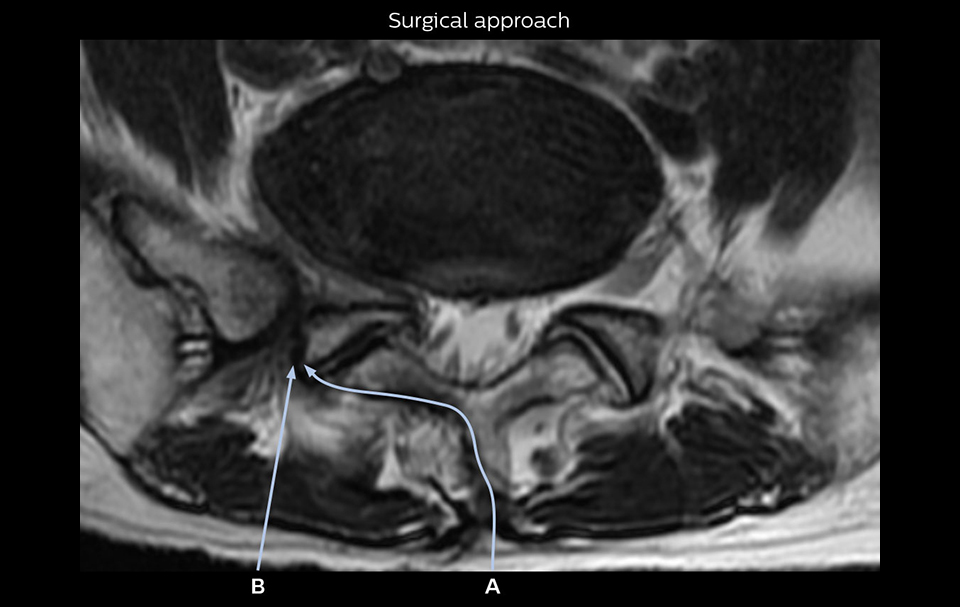

“Recently, the two surgical methods extreme and oblique lateral interbody fusion (XLIF and OLIF) have become mainstream for minimally invasive treatment of lumbar spinal canal stenosis and intervertebral foramen stenosis. With these surgical techniques, the spine is approached from the flank, and prior knowledge of the exact anatomy of the lumbosacral plexus would be extremely helpful. To that end, high slice resolution (less than 1 mm acquisition) that enables sharper sagittal MPR images will be needed.”

“Although symptoms of typical disc herniation and atypical hernia are very similar, the actual site of herniation is different. It is therefore important to characterize the nerve’s condition both inside and outside of the intervertebral foramina. “Conversely, if we see no abnormality in NerveVIEW, we can assume at least that there is no severe condition that requires surgery. Like this, it can help us avoid unnecessary surgery. NerveVIEW can have a tremendous impact in this way.”

“For example, in sagittal images, when the presence of fat is observed in the intervertebral foramen, it suggests that there is a margin around the nerve. Similarly, the absence of fat indicates that the nerve is being compressed. So, we used to deduce nerve compression indirectly. With NerveVIEW, however, we can observe the condition of the nerves directly, regardless of the presence or absence of fat. We always prefer such direct observation of anatomy over having to make an inference about it.”